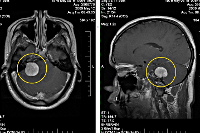

Подозрение на объемное образование головного мозга является однозначным показанием к проведению компьютерной или магнитно-резонансной томографии. КТ головного мозга позволяет визуализировать опухолевое образование, дифференцировать его от локального отека церебральных тканей, установить его размер, выявить кистозную часть опухоли (при наличии таковой), кальцификаты, зону некроза, кровоизлияние в метастаз или окружающие опухоль ткани, наличие масс-эффекта. МРТ головного мозга дополняет КТ, позволяет более точно определить распространение опухолевого процесса, оценить вовлеченность в него пограничных тканей. МРТ более результативна в диагностике не накапливающих контраст новообразований (например, некоторых глиом головного мозга), но уступает КТ при необходимости визуализировать костно-деструктивные изменения и кальцификаты, разграничить опухоль от области перифокального отека.